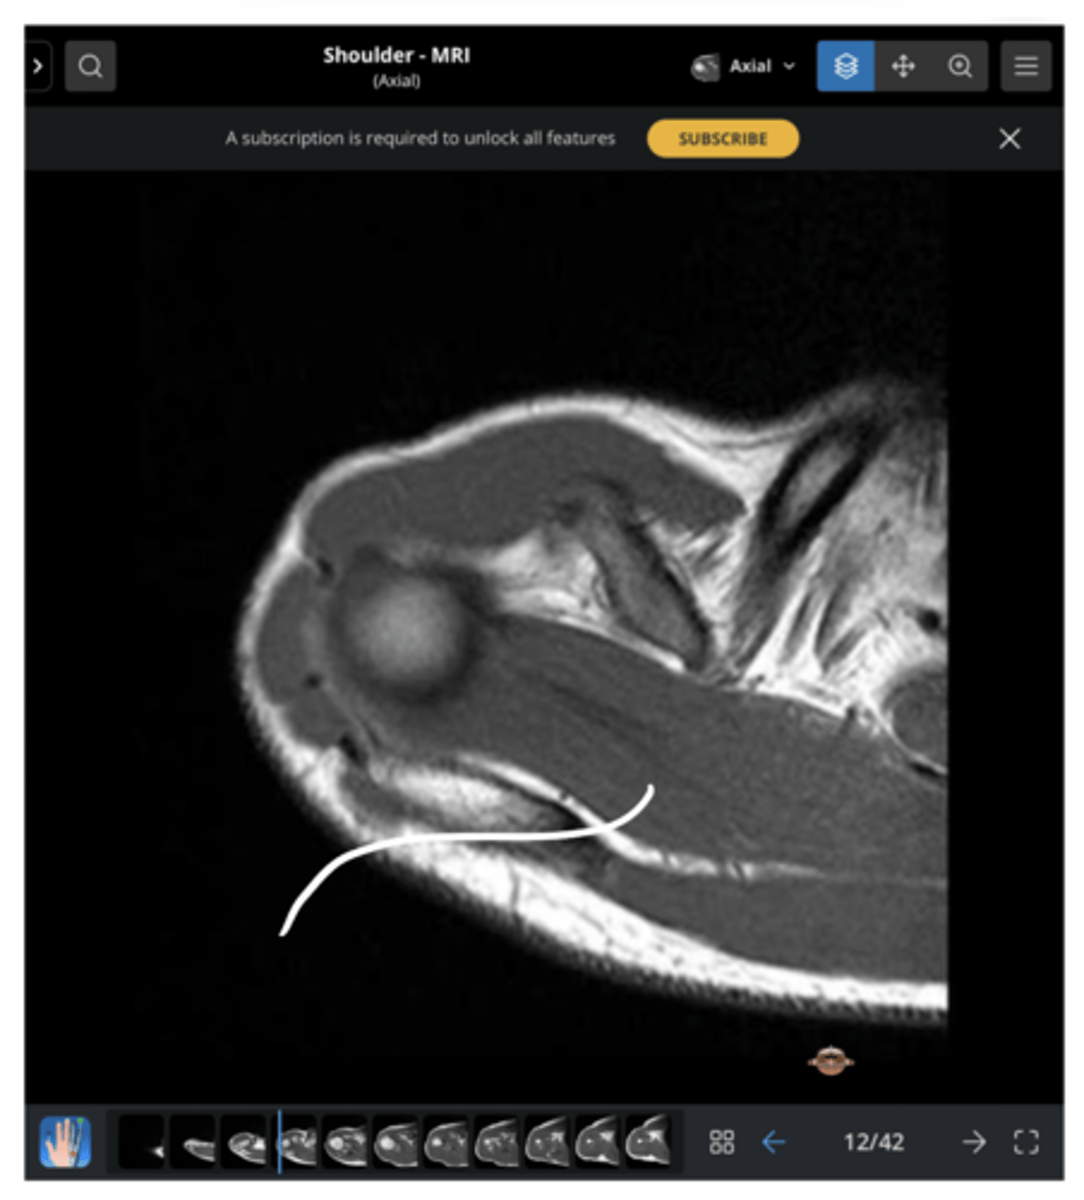

An axial view of the subscapularis tendon wrapping around the anterior portion of the humerus & the infraspinatus tendon on the back side

What is this image depicting?

1. Subscapularis (superiorly)

2. Infraspinatus (inferiorly)

Which structures are being pointed to in this image?